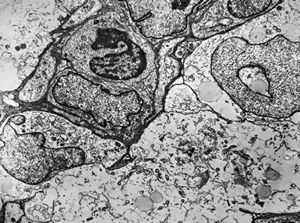

F,13y. | n.suralis … axonal neuropathy … Charcot-Marie-Tooth disease